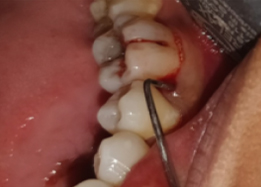

Half of Lower molar tooth along with diseased root removed & rest part is saved.

PRE OP Clinical Photograph Measuring Probing Depth